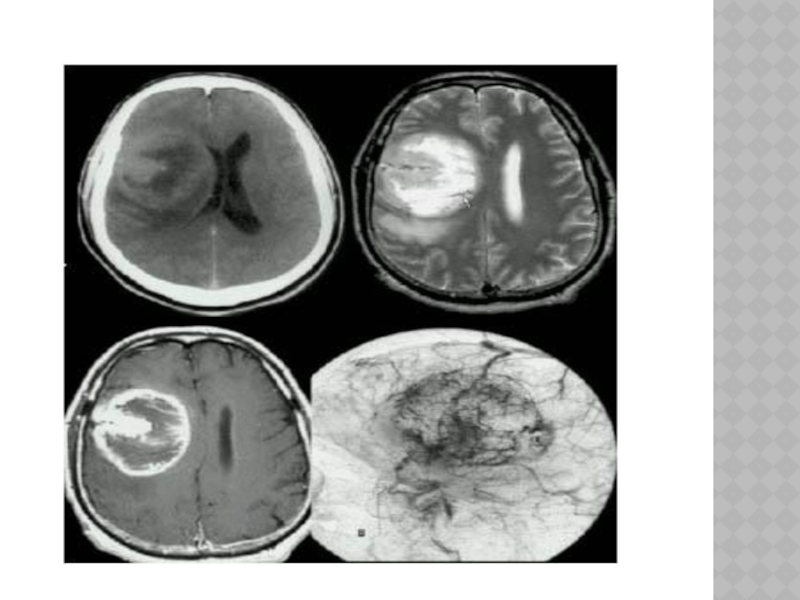

Слайд 113ОПУХОЛИ ГОЛОВНОГО МОЗГА

Классификация:

1) от вида ткани, из которой они растут,- менингеомы,

арахноэндотелиомы, глиомы, астроцитомы и т.д.;

2) от локализации - внемозговые, внутримозговые, больших полушарий, мозжечка, ствола, гипофиза и др.

3) от доброкачественности - доброкачественные, злокачественные;

4) от расположения по отношению к намету мозжечка (супратенториальные - расположенные над наметом, субтенториальные);

5) от локализации основного очага - первичные, растущие из тканей мозга, и метастатические, занесенные из других систем организма.

ОПУХОЛИ ГОЛОВНОГО МОЗГА Классификация:1) от вида ткани, из которой они растут,- менингеомы, арахноэндотелиомы, глиомы, астроцитомы и т.д.;

Доброкачественными считаются ограниченные опухоли с медленным ростом, злокачественными - опухоли, обладающие

инфильтративным ростом.

Опухоли составляют 4,5% всех органических заболеваний головного мозга и встречаются преимущественно в возрасте 20-40 лет.

Доброкачественными считаются ограниченные опухоли с медленным ростом, злокачественными - опухоли, обладающие инфильтративным ростом. Опухоли составляют 4,5% всех

Слайд 115КЛИНИКА

-симптомы зависят от локализации опухоли.

-при опухолях полушарий -очаговые симптомы, общемозговые.

-при опухолях ствола, мозжечка на первый план выступают общемозговые симптомы, что обусловлено ограниченным пространством задней черепной ямки, сдавлением ликворопроводящих путей.

-при опухолях гипофиза ранними признаками являются нарушения эндокринных функций (расстройство менструального цикла, ожирение, усиленный рост пальцев рук, ног и т.д.).

КЛИНИКА-симптомы зависят от локализации опухоли. -при опухолях полушарий -очаговые симптомы, общемозговые. -при опухолях ствола, мозжечка на первый

Слайд 117ДИАГНОСТИКА

Электроэнцефалография, эхоэнцефалоскопия, рентгенография черепа, ангиография, компьютерная рентгеновская и магниторезонансная томография, офтальмологическое

обследование.

ДИАГНОСТИКАЭлектроэнцефалография, эхоэнцефалоскопия, рентгенография черепа, ангиография, компьютерная рентгеновская и магниторезонансная томография, офтальмологическое обследование.

Слайд 122ЛЕЧЕНИЕ

-хирургическое вмешательство

-симптоматическая терапия- дегидратационные средства, анальгетики, противосудорожные препараты (финлепсин, корбамазепин, соли

вальпроевой кислотыи др.) - при опухолях гипофиза -рентгенотерапия(эпендиома, медуллобластома, герминома, аденома гипофиза) -химиотерапия- прокарбазин, ломустин, винкристин (глиомы, астроцитомы), при пинеобластомах, медуллобластомах, герминомах наряду с радиотерапией используются производные платины (цисnлатин, карбоплатин), этопозид, блеоиин.

ЛЕЧЕНИЕ-хирургическое вмешательство-симптоматическая терапия- дегидратационные средства, анальгетики, противосудорожные препараты (финлепсин, корбамазепин, соли вальпроевой кислотыи др.) - при опухолях